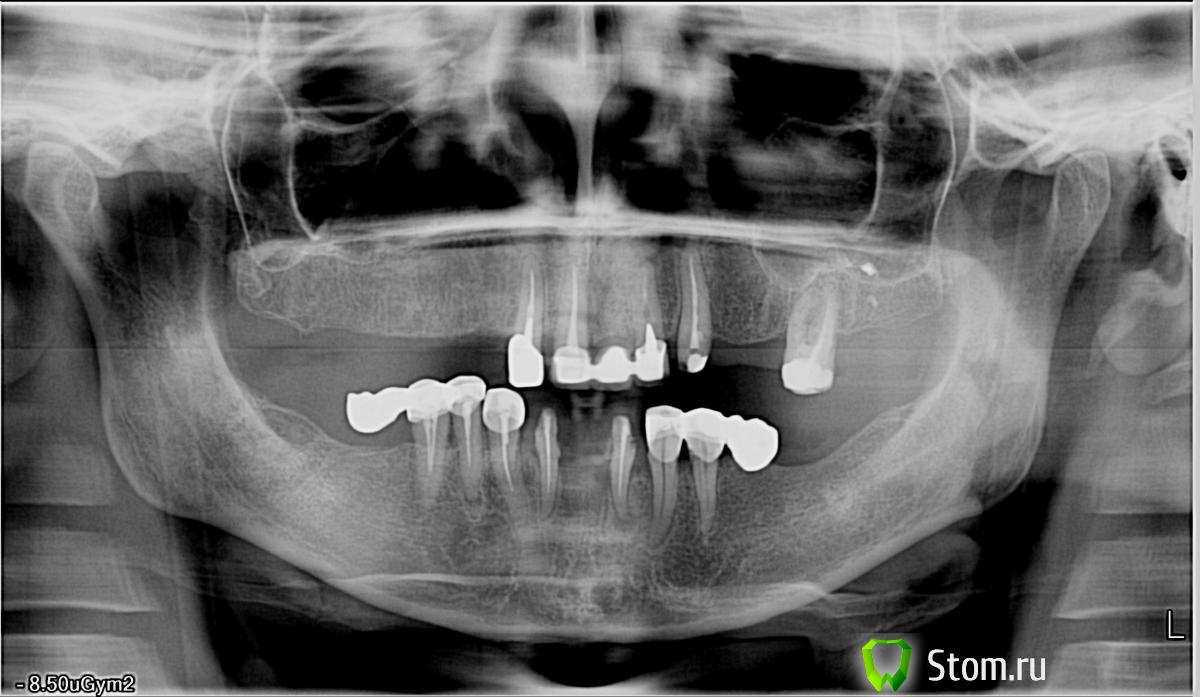

zubnik Опубликовано 22 февраля, 2012 Поделиться Опубликовано 22 февраля, 2012 Доброго времени суток! Обратилась пациентка с целью протезирования. Очень хотелось бы услышать ваше мнение по поводу плана лечения. Спасибо! Ссылка на комментарий

hogsmeed Опубликовано 22 февраля, 2012 Поделиться Опубликовано 22 февраля, 2012 Снять все32,44 удалитьэндо и переэндо практически всеа дальше.............тыща вариантов Ссылка на комментарий

pit Опубликовано 22 февраля, 2012 Поделиться Опубликовано 22 февраля, 2012 Доброго времени суток! Обратилась пациентка с целью протезирования. Очень хотелось бы услышать ваше мнение по поводу плана лечения. Спасибо!Кейс просто волшебный) Удалить все свои зубы; 8-10 имплантов вверху и 8 внизу и немедленно нагрузить.Или же посохранять свои зубы, тогда эндо и ретрит всех зубов, ну и в отсутствующие закрутить импланты.Ну или вариант со съемными протезами..., но это как-то не очень будет 1 Ссылка на комментарий

Orient Опубликовано 22 февраля, 2012 Поделиться Опубликовано 22 февраля, 2012 смотря что с финансами у пациента!1.эндо, и два бюгеля2. импланты и =>... Ссылка на комментарий

Afffinity Опубликовано 23 февраля, 2012 Поделиться Опубликовано 23 февраля, 2012 смотря что с финансами у пациента!Точно подмечено. 32,44 удалитьзачем же так сразу, для начала пробовать перелечить, а потом думать об удалении.ИМХО, послеперелечивания по возможности сделать мосты, а все остальное либо бюгели либо импланты Ссылка на комментарий

zubnik Опубликовано 23 февраля, 2012 Автор Поделиться Опубликовано 23 февраля, 2012 Большое спасибо! С финансами не очень, на импланты не тянет. Если сохранять зубы, то что делать с выдвинувшимися 45,44 зубами, поднимать прикус не куда, удалять только если. Фото в профиль и модели выложу как только сделаю. Ссылка на комментарий

Skip Опубликовано 23 февраля, 2012 Поделиться Опубликовано 23 февраля, 2012 Всегда стараюсь относиться к пациентам как к себе самому, но здесь не знаю как поступить. "Не куда" , в смысле прикус не снижен, если еще разобщить, то губы не будут смыкаться, вернее будут, но с напряжением. Скип, очень внимательно всегда читаю ваши посты, посоветуйте пожалуйста, как быть. Мне конечно до Вас очень далеко пока, видел Ваши работы, смотрю на них как на нечто фантастическое, тем более, что не владею ортодонтией. Это не заискивание, просто очень давно читаю этот форум и поэтому сложилось такое мнение. Кстати, огромную благодарность хочу выразить всем участникам, так как очень-очень-очень много почерпнул из форума. Спасибо! Прежде, чем задаваться вопросом "КАК БЫТЬ..?", Вам сначала необходимо разобраться с другим вопросом, а именно - "ПОЧЕМУ..?" Почему нижние зубы справа уже коснулись верхнего альвеолярного отростка? Вы говорите, что они (зубы) выдвинулись и я тоже могу вполне допустить это. Но, я также вижу и то, что нижняя челюсть смещена в эту же сторону. Тогда встаёт другой вопрос, это что, то положение н.челюсти, которое наиболее оптимально для пациента..? Я уверен, что нет. Идём дальше, а как нам узнать/определить это оптимальное, физиологическое, для этого конкретного пациента, положение нч? И здесь мы задаёмся ещё одним вопросом, а именно - Где нижняя челюсть желает быть? Буквально спрашиваем: - Нижняя челюсть, ты где хочешь быть? Пытаться искуственно указать нижней челюсти, где ей следует находиться, не сработает и для этого мы должны выбрать определённую стратегию регистрации прикуса. Если есть проблемы с ВНЧС - одна стратегия, если нет проблем - другая, НО, у меня первая регистрация прикуса никогда не бывает окончательной, поэтому меня на первом этапе мало беспокоит, как пациент будет смыкать свои губы. Ссылка на комментарий